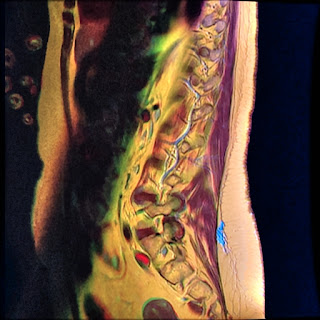

Color MRI of the Lumbar vertebrae

- T1W FSE in red channel

- T2W frFSE in green channel

- STIR in blue channel.

- Yellow: Orange

- Water: Green-Blue

- Muscles: Purple

- T1W TSE in red channel

- T2W TSE in green channel